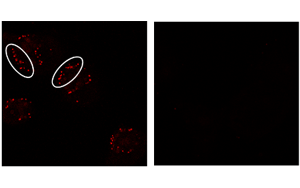

熊本大學(xué)的一組研究人員發(fā)現(xiàn)了導(dǎo)致神經(jīng)退行性疾病(如帕金森?。┑挠泻Φ鞍踪|(zhì)聚集體形成的突破性機(jī)制。由Norifumi Shioda教授和Yasushi Yabuki副教授領(lǐng)導(dǎo)的研究小組首次發(fā)現(xiàn),一種名為G-四重復(fù)合物(G4s)的獨(dú)特RNA結(jié)構(gòu)在促進(jìn)α-突觸核蛋白(一種與神經(jīng)變性相關(guān)的蛋白質(zhì))的聚集中起著核心作用。通過證明抑制G4組裝可能潛在地阻止突觸核蛋白病的發(fā)生,這一發(fā)現(xiàn)將G4定位為這些疾病早期干預(yù)的有希望的靶點(diǎn)。